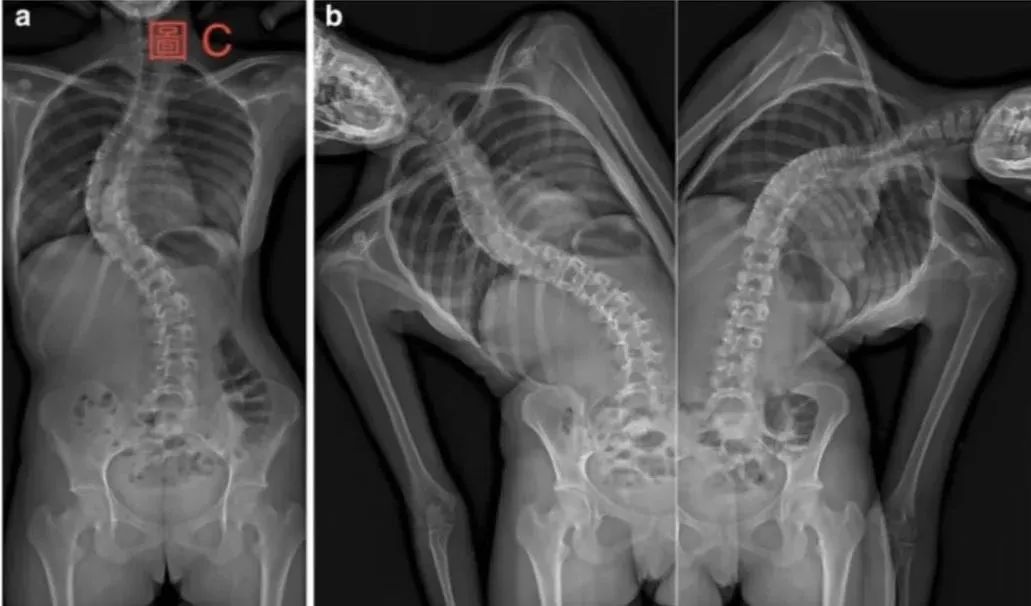

这类的侧弯大多是因为先天脊柱结构不良等导致脊柱侧弯合并旋转进而无法直立。而此类的侧弯大致上是无法恢复的形态。临床当中大多数选择利用开刀的方式来调整。

为临床较少见的结构性脊柱侧弯,最左图可看出在最左侧为直立站姿下脊柱呈现胸椎向右以及腰椎向左的曲度(X光片跟我们会呈现相反的方向)。中间图表示请患者往右侧弯,胸椎的曲度不会因为动作而改善,这个我们称脊柱已经呈现结构性的改变了,但在最右图,我们请患者往左侧弯,可以看到腰椎因为左侧弯而顺应的回复曲度,因此我们称腰椎为非结构性的改变。我们解释腰椎的曲度是因为胸椎的结构性改变而导致发生代偿性曲度,以顺应我们的身体保持在中线的功能。